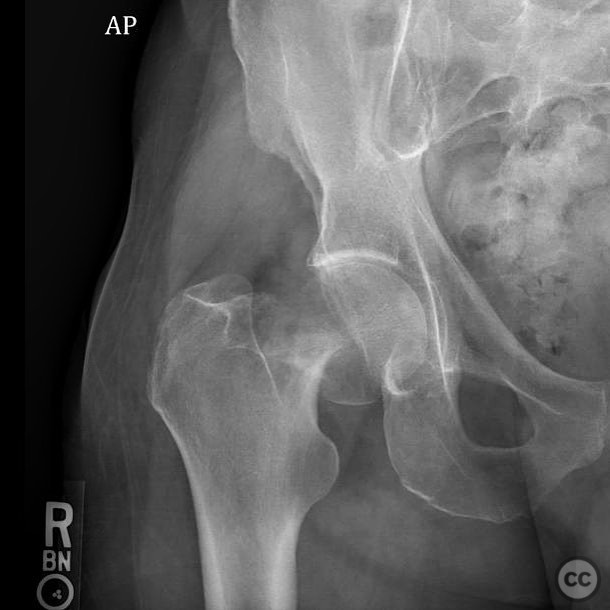

Clinical and radiological findings:  A 62-year-old male presented following a fall from standing height, resulting in a displaced subcapital femoral neck fracture. The patient has a complex medical history including substance abuse (methamphetamine and cocaine), cirrhosis, diabetes, and open draining foot wounds. Radiographs confirmed a displaced femoral neck fracture, classified as AO/OTA 31-B2.